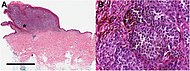

Histopathologic types[edit | edit source]

An anal melanoma

Melanoma is a type of neuroectodermal neoplasm.[76] There are four main types of melanoma:[77]

Type Features Incidence[77][notes 1] Photograph Micrograph

Superficial spreading melanoma Melanoma cells with nest formation along the dermo-epidermal junction. 70% Superficial spreading melanoma in situ on dermoscopy.jpg Histopathology of superficial spreading melanoma.jpg

Nodular melanoma Grows relatively more in depth than in width. 15% - 20% Photography of nodular melanoma.jpg Histopathology of nodular melanoma.jpg

Lentigo maligna melanoma Linear spread of atypical epidermal melanocytes as well as invasion into the dermis.[78] 5% - 10% Photograph of lentigo maligna melanoma.jpg Histopathology of lentigo maligna melanoma.jpg

Acral lentiginous melanoma Continuous proliferation of atypical melanocytes at the dermoepidermal junction.[79] 7% - 10% Photography of a large acral lentiginous melanoma.jpg Histopathology of invasive acral lentiginous melanoma.jpg